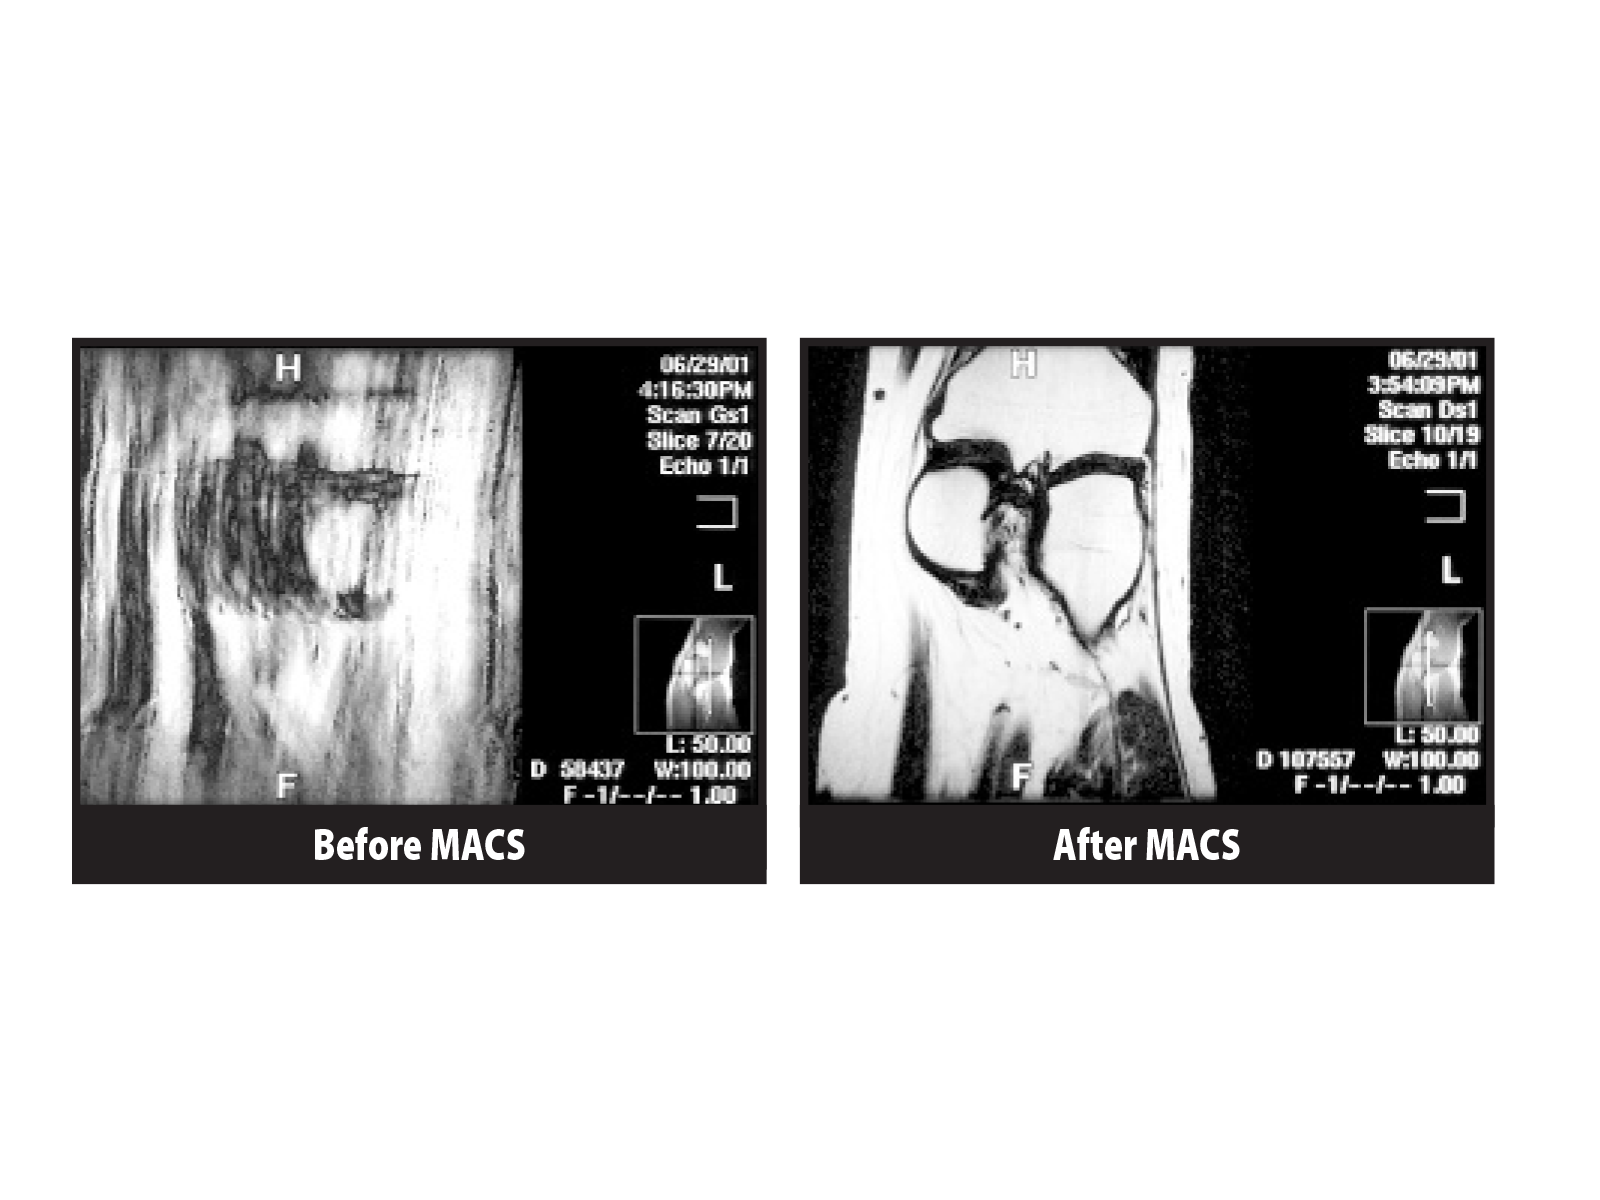

MACS/D (Magnetic Active Compensation System) for MRI

Magnetic active compensation system stabilizes MRI environments by canceling dynamic magnetic interference and maintaining consistent field conditions, even in demanding urban or industrial locations.

Magnetic active compensation system provides high-performance attenuation of fluctuating magnetic fields that can disrupt MRI imaging quality and system stability. Using digital signal processing, tri-axial coil drivers, and ACR technology, the system corrects both AC and DC environmental interference over a wide frequency range. It is designed for challenging locations affected by elevators, trains, vehicles, and nearby electrical or magnetic equipment.